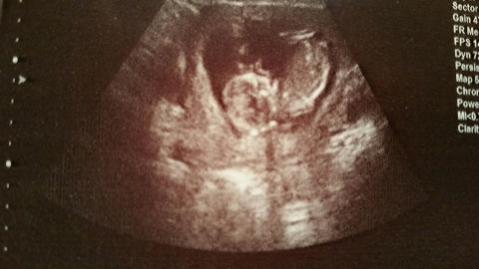

Hi ladies! I haven't been in here in a while and I have another baby on the way. (I didn't sway) I have 2 u/s one from last week at 12.5 and one from today at 13.5 please nub guess if you can or let me know if there is no nub (I'm not good at spotting them). TIA